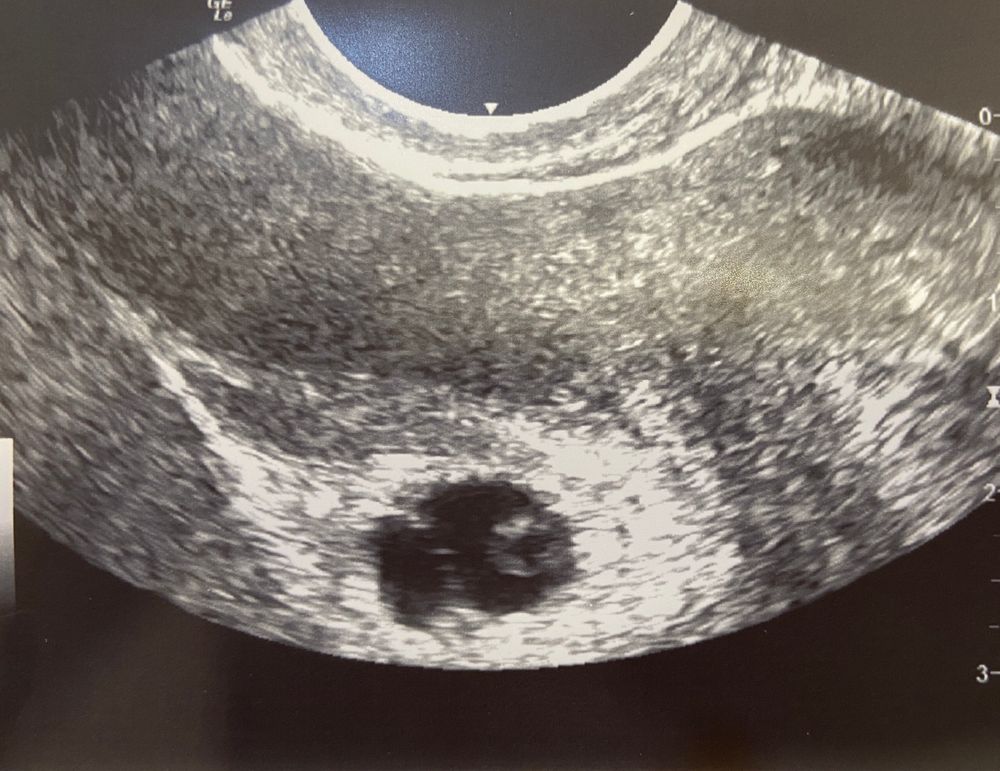

Послушаю вас… что скажете? Я пока в шоке…

Беременность 5 и 5 дней… выделения практически прекратились, сами, без таблеток… Гинеколог ошарашила….

дописываю: она не исключает двух малышей, но с один проблема… меньше и жм нету ещё… исходы рассказала….

Похоже на двойню) Но жм пока только один, всякое может быть

Рано очень делать выводы! Мне на 6+2 второго не нашли, а в 8+2 ошарашили что было двое. На снимке не вижу двух.